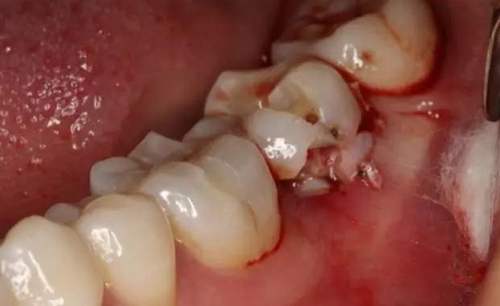

圖3.拔除47后的牙槽窩影像:

12.jpg